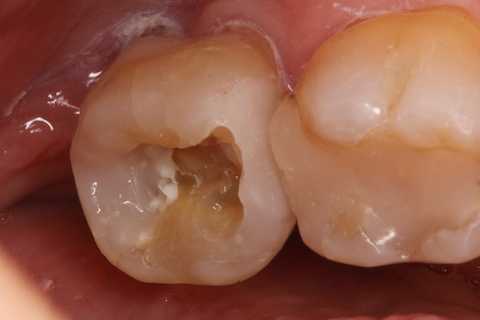

この症例は歯根内部をいじられていないので、根管治療は難しくない。CRで歯冠を再建するのが難しかった。

再建が終わった後で、内部の治療をしてCRで埋め戻している。